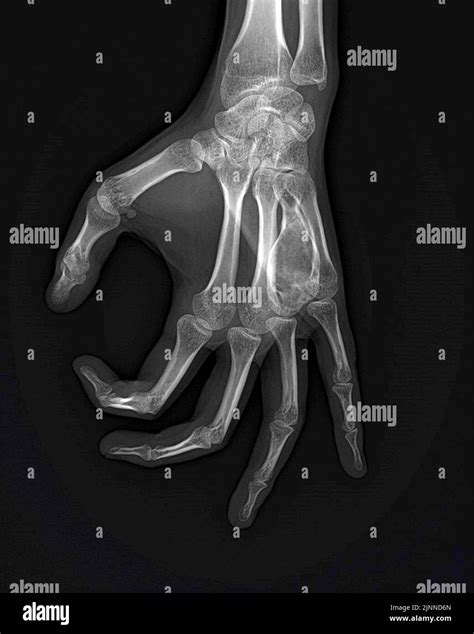

Discovering a lump on your wrist or palm can be a source of immediate anxiety, leading many to search for information regarding a G cyst hand. In medical terms, this is commonly referred to as a ganglion cyst, which is a noncancerous lump that most frequently develops along the tendons or joints of your wrists or hands. Understanding what these cysts are, why they form, and how they are typically managed is essential for anyone experiencing discomfort or aesthetic concern from these fluid-filled bumps.

A G cyst hand is essentially a sac filled with a jelly-like fluid. These cysts arise from the joint capsule or tendon sheaths in the wrist or hand. While the exact cause remains somewhat elusive, they are believed to occur due to minor, repetitive trauma or irritation to the joint or tendon area, which triggers the leakage of joint fluid into the surrounding tissue.

When you visit a doctor for a G cyst hand, the diagnosis is usually straightforward. The physician will begin with a physical examination, checking the texture of the lump and testing its mobility. They may also shine a light through the cyst (transillumination) to see if it is translucent, which strongly suggests it is fluid-filled rather than solid.

• X-rays: These do not show the cyst itself but help rule out underlying bone issues or arthritis in the joint.